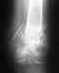

Указаны области переломов. Что-то там уже появляется. Все сделано хорошо, не оснований ожидать проблем.

Снимков верхнего конца стержня нет. Видимо, синтез компрессионно-динамический, т.е. нагрузка передается через зону перелома. Ее можно дозировать по хромоте. Избыточную нагрузку переносить на костыли или трость в противоположной руке. То есть опираться на ногу так, чтобы не хромать. Но важнее пораньше разработать движения в голеностопном суставе. Особенно стопу на себя чтобы можно было потянуть на тот же угол, что на здоровой ноге. Сесть на корточки.